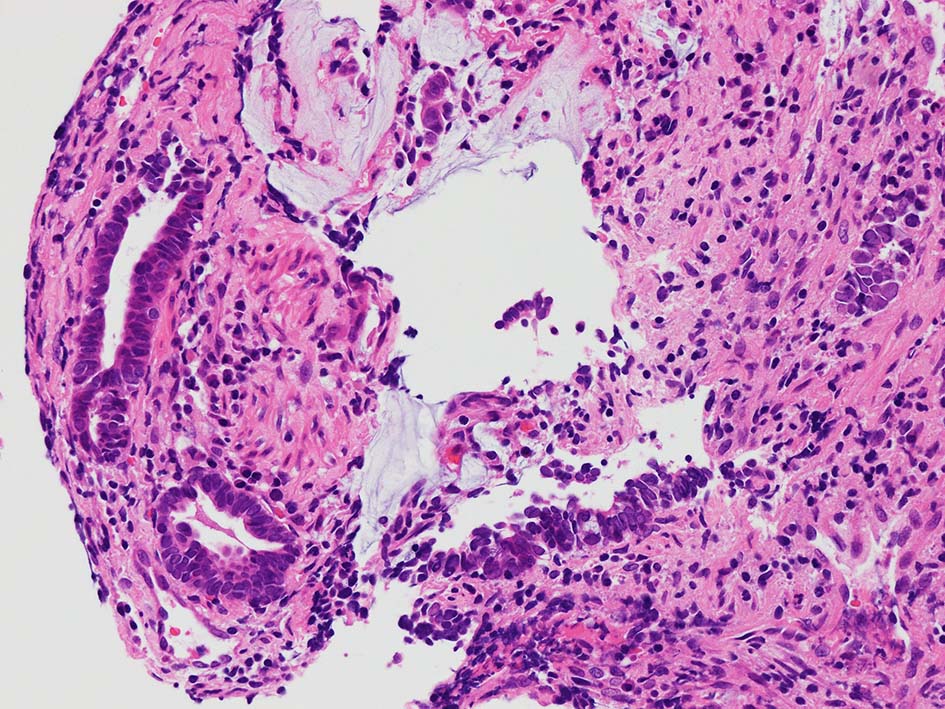

desmoplastic fibrosis, 粘液浸潤のみられる組織片にはsig, porのadenocarcinoma浸潤が確認される.